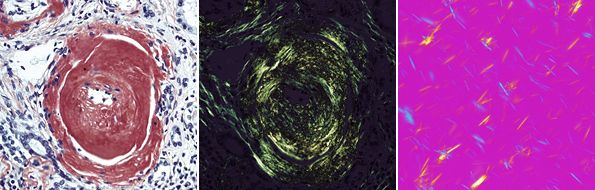

図16 組織切片のアミロイド観察と尿酸ナトリウムの偏光観察

図16 組織切片のアミロイド観察(左:明視野観察 中:偏光観察)と尿酸ナトリウムの偏光観察(右:尿酸結晶観察)

偏光観察法(P、PL:Polarized Light microscopy)

岩石、鉱物の結晶の観察や、物質の複屈折性(入射した光が2つの屈折光に分かれる性質)の検出、測定を行うのに適した観察方法である。

顕微鏡に2枚の偏光板を装着し、偏光の干渉を利用して複屈折性の存在する部分を明暗や色のコントラストに置換えて観察する。

回転ステージを用いて標本を回転させると、複屈折性のある部分が45°ごとに暗く見えたり(消光位)、明るく見えたり(対角位)する。